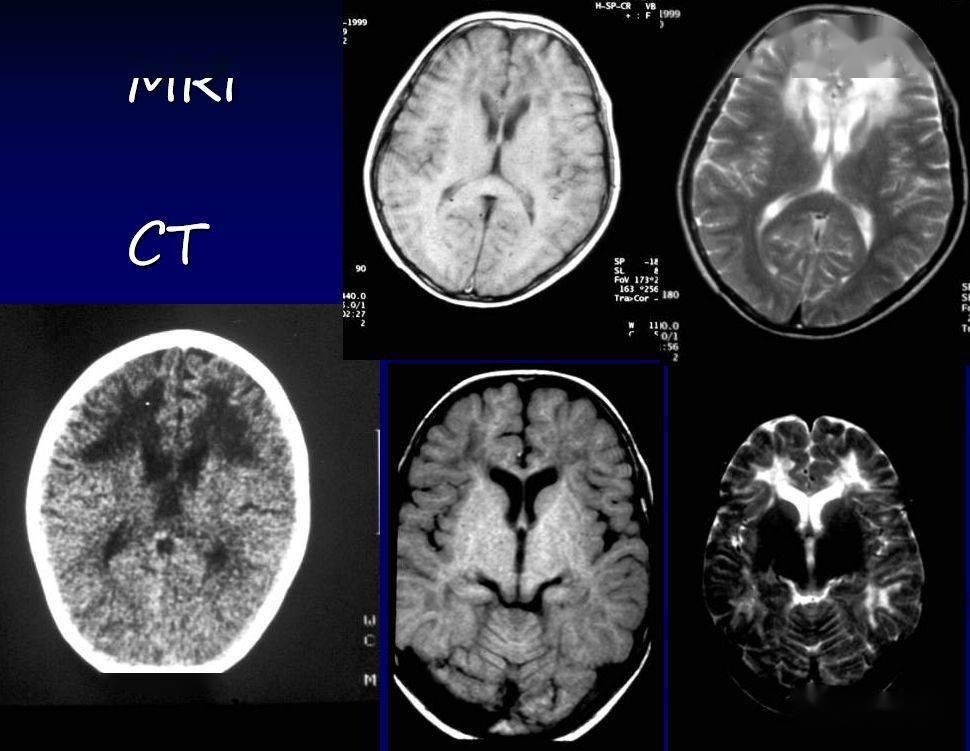

双侧额叶脑白质

双侧基底节区,半卵圆中心多发脑白质疏松

双侧额顶枕叶脑白质区示对称性低密度区,边界欠清.

脑白质病变的影像学鉴别诊断

ct 双侧大脑半球脑白质密度减低,脑沟显示不清,脑室变小,中线结构居中

头颅ct:双侧基底节区多发腔梗,脑白质变性.

>> 文章内容 >> 脑白质病影像学诊断 双侧半卵圆中心,侧脑室旁可见